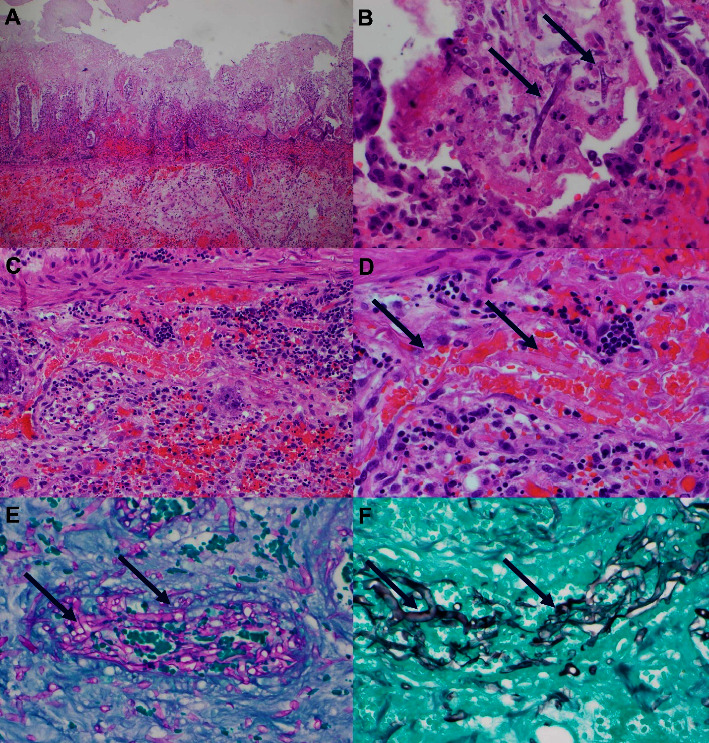

Although fungal infections causing intestinal perforation and necrosis are rare, they can be particularly dangerous in immunosuppressed patients, often leading to increased mortality rates and poor prognoses. Candida species are typically surface fungi, but in patients with compromised immune systems, they can invade the small intestine and cause angioinvasive infections. A case study involving a 30-year-old female with acute myeloid leukemia (AML) illustrates this phenomenon. The patient was presented with symptoms of abdominal pain, fever, diarrhea, recurrent episodes of intestinal necrosis, hematomas due to thrombocytopenia, and subsequent postoperative enterocutaneous fistulas. Extensive testing ruled out other possible causes of intestinal necrosis and enteritis, including Crohn's and CMV diseases. Candida guilliermondi was ultimately identified in blood cultures from the periphery, peritoneal fluid, and intestinal biopsy of respected sections, indicating that it was responsible for intestinal invasion and necrosis. The patient was then treated with amphotericin B, cefepime, and metronidazole. This case highlights the potential severity of fungal infections in immunosuppressed patients, particularly Candida species, and the importance of prompt diagnosis and appropriate treatment.